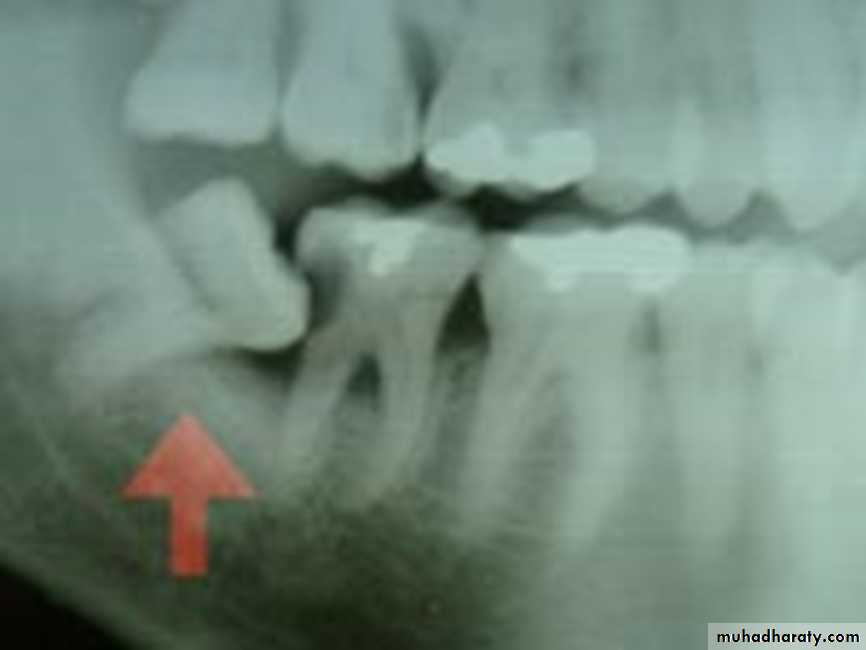

Dentigerous cyst causes tooth impaction

Mosul university- College of dentistry-oral & maxillofacial surgery department